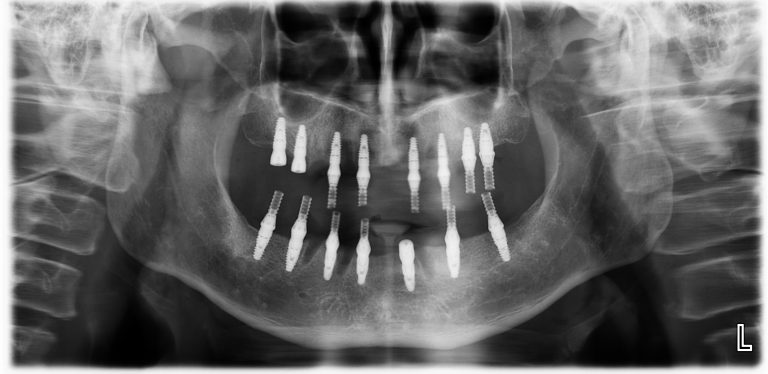

全口重建最新的觀念 All on X,X 代表的是病人所需的植體顆數(單顎最少 4 支,至多 10 支)。植體顆數會依照病人不同飲食習慣、年齡、性別、對咬牙狀況,完全100%客製化設計病人專屬治療計畫。新的觀念 All on X 才能帶給病人更長久且更穩定的治療結果。

上顎 All on 8,下顎 All on 7

上顎 All on 8

- 植牙手術:手術日早上,郭光哲醫師會依照治療計畫在每顎植入植體,植牙過程在舒眠麻醉下執行,並由專業的麻醉科醫師協助監控,讓患者一覺起來輕鬆完成手術,毫無壓力。為了追求完美,郭光哲醫師在每個 All on X 手術中都會搭配最新 Navident 4 (AR擴增實境數位導航),完美執行精準與安全。手術完成後,需要等待2到6個月,讓植體與骨頭完全密合。接著郭光哲醫師會開始製作正式假牙讓患者試戴,並根據病人的反饋進行調整,最後製作出兼具美觀與功能的正式假牙。

植體品牌和植體支數:郭光哲醫師會根據病人骨頭的條件、身體狀況、飲食習慣,推薦最適合病患的植體品牌和植體支數,依照植體品牌而有不同的收費和保固。瑞士 Straumann® 植體擁有卓越的骨再生、骨整合的能力,植體本身採用 Roxolid® 專利材質,不論是硬度或耐用度都被全世界牙醫共同認可,為郭光哲醫師最推薦品牌,也是追求品質、穩定的患者首選品牌。